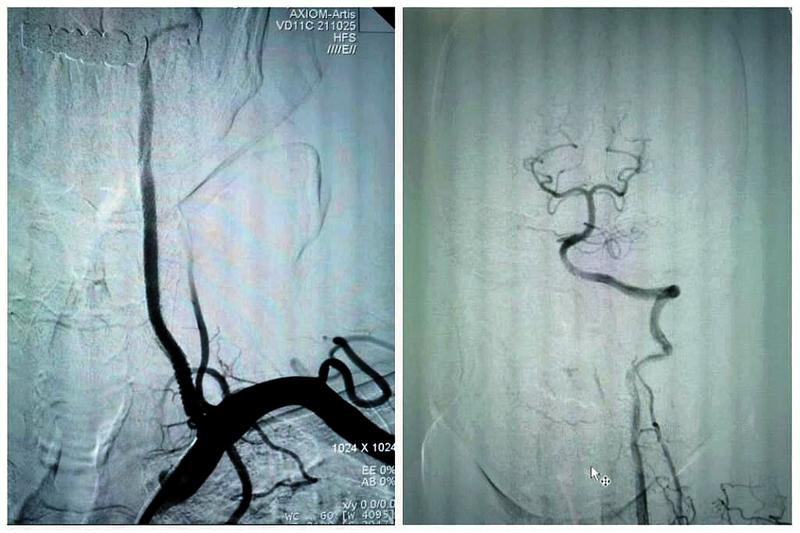

最终,在患者入院第4天,张桂莲教授带领的介入团队选择局麻条件下为患者成功实施了神经介入领域的高难度手术—左侧无残端椎动脉长节段慢性闭塞再通术。因术前清晰的影像显影及准确的体外定位标记,左侧优势椎动脉顺利开通,手术耗时仅仅约90分钟。术中及术后患者配合良好,无任何不适。出院前复查头颈一体化超声提示左侧椎动脉支架位置良好,血流通畅,颅内血流速度及频谱未见明显异常。充分向患者及家属告知出院注意事项及复查时间后,目前该患者已顺利出院。

双侧椎动脉闭塞是“天堑”,其所导致的后循环缺血事件是“天灾”,严重影响患者生活质量,甚至随时危及患者生命。无残端的双侧椎动脉慢性闭塞再通,是神经介入领域的最高难度手术之一,其原因在于根本无法确定手术位点。面对患者及家属的信任,我院张桂莲主任领导的神经内科介入团队与李晓会教授带领的影像学团队不忘初心、紧密合作、敢于挑战、乐于奉献,最终不负患者及家属重托将无残端长节段椎动脉闭塞的“天堑”变为后循环正常血流的“通途”。